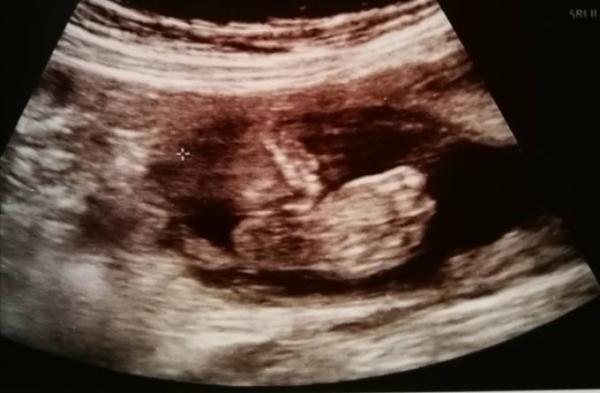

Juhuu das Outing für unsere Prinzessin wurde heute definitiv bestätigt, ich bin so Happy zu meinen zwei Prinzen jetzt noch eine Prinzessin zu bekommen, Organe sehen auch super aus, sie scheint sehr groß zu sein, Gewicht liegt bei 500 g und Größe ca. 35 cm...das möchte sie bei der nächsten Untersuchung nochmal kontrollieren, aber ansonsten alles bestens, sie haben heute auch das erste ctg geschrieben, was der kleinen Maus natürlich überhaupt nicht gefiel ich habe den größten heute später zur schule gebracht und er durfte dabei sein und erfahren das er eine kleine Schwester bekommt, hach es ist einfach so eine wunderbare Zeit

Bild zu Outing - Forum für April - Mamis